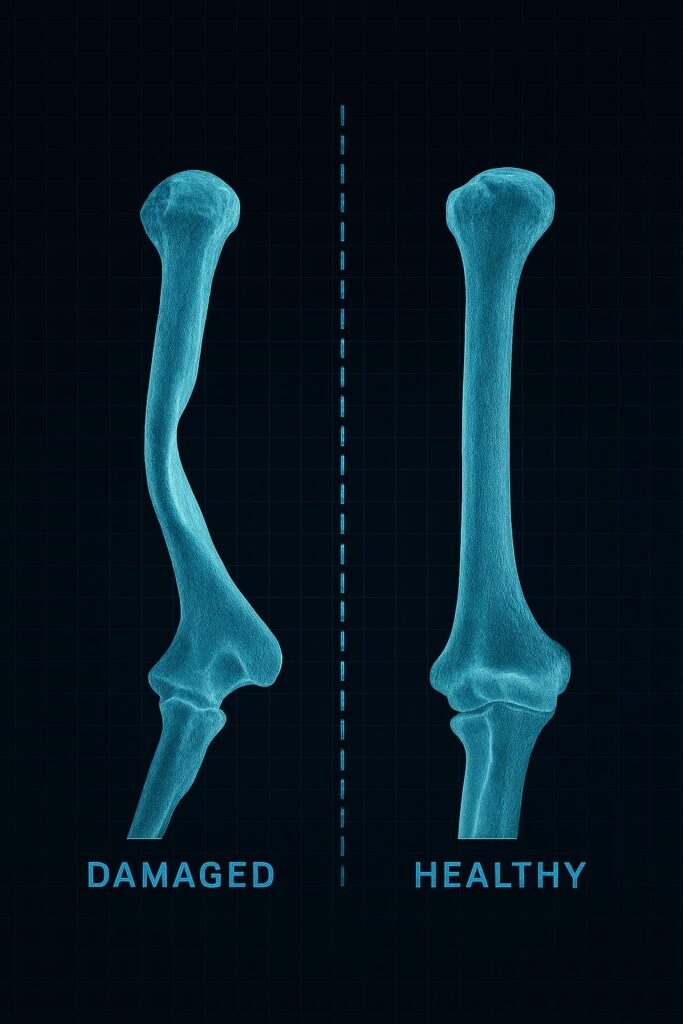

Los TAC se trasladaron al laboratorio 3D, donde con aparatos e instrumental sofisticado, junto a ingenieros muy preparados (pueden reconstruir el esqueleto de una persona), imprimimos el húmero derecho, dañado, y también el sano, permitiéndonos una comparación perfecta y estudiar el tipo de cirugía que debíamos practicar.

Por otra videoconferencia (esta vez, de madrugada), él estaba corriendo en Misano. Allí le mostré sus húmeros y vio claramente cuál era el problema y entonces le expliqué lo que se podía hacer.